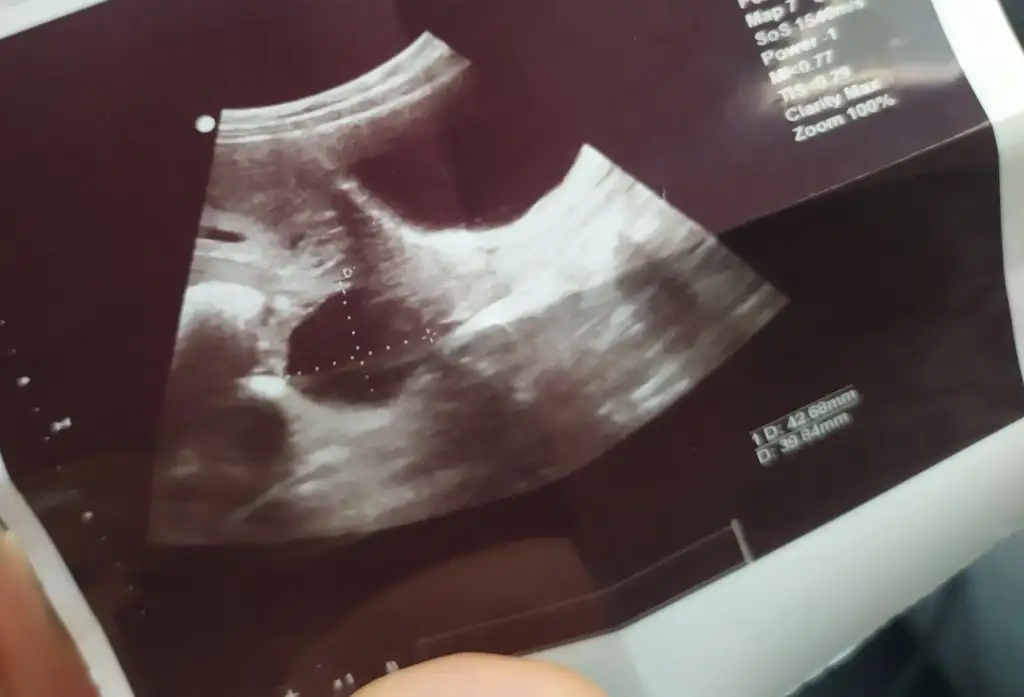

Atın resimleri bakalım doktorunuz sorun yok dediyse korkmayınKızlar hepinize merhaba 8 haftalık hamileyim. 2 gün önce kontrole gittiğimde kalp atışlarını duyduk, ve doktor ultrasonla baktığı sırada kistin var ama gebeliğe bağlı oluşan bir kist gibi, korkma gebelikte olur 12 14. Haftada geriler dedi. Şuan herşey yolunda dedi ve odadan çıkmadan ultrason görüntülerini verdi. Size sorum biraz sonra atacağım fotoğraflarda birinde bebeğim var, ve bebeğimi çevreleyen kese fasulye şeklinde. Fakat diğerini anlamış değilim. Bu yuvarlak şekil kist mi, yoksa gebelik kesesi mi? Ultrason aletini tutuş açısına göre kese şekli değişiyor mu? Bunun üstünden cinsiyet tahmini yapılıyormuş. Lütfen yardımcı olun ♥♥♥♥♥

Bilmiyorum ki, inşallah benzer durum tecrübe etmiş arkadaslarımız çıkar..Dediğiniz gibi fasulye şeklinde olan kese içinde bebeğiniz var diğer yuvarlaklar kist olmalı emin değilim yanlış bilgi olmasın kistse bu kadar büyük oluyormu